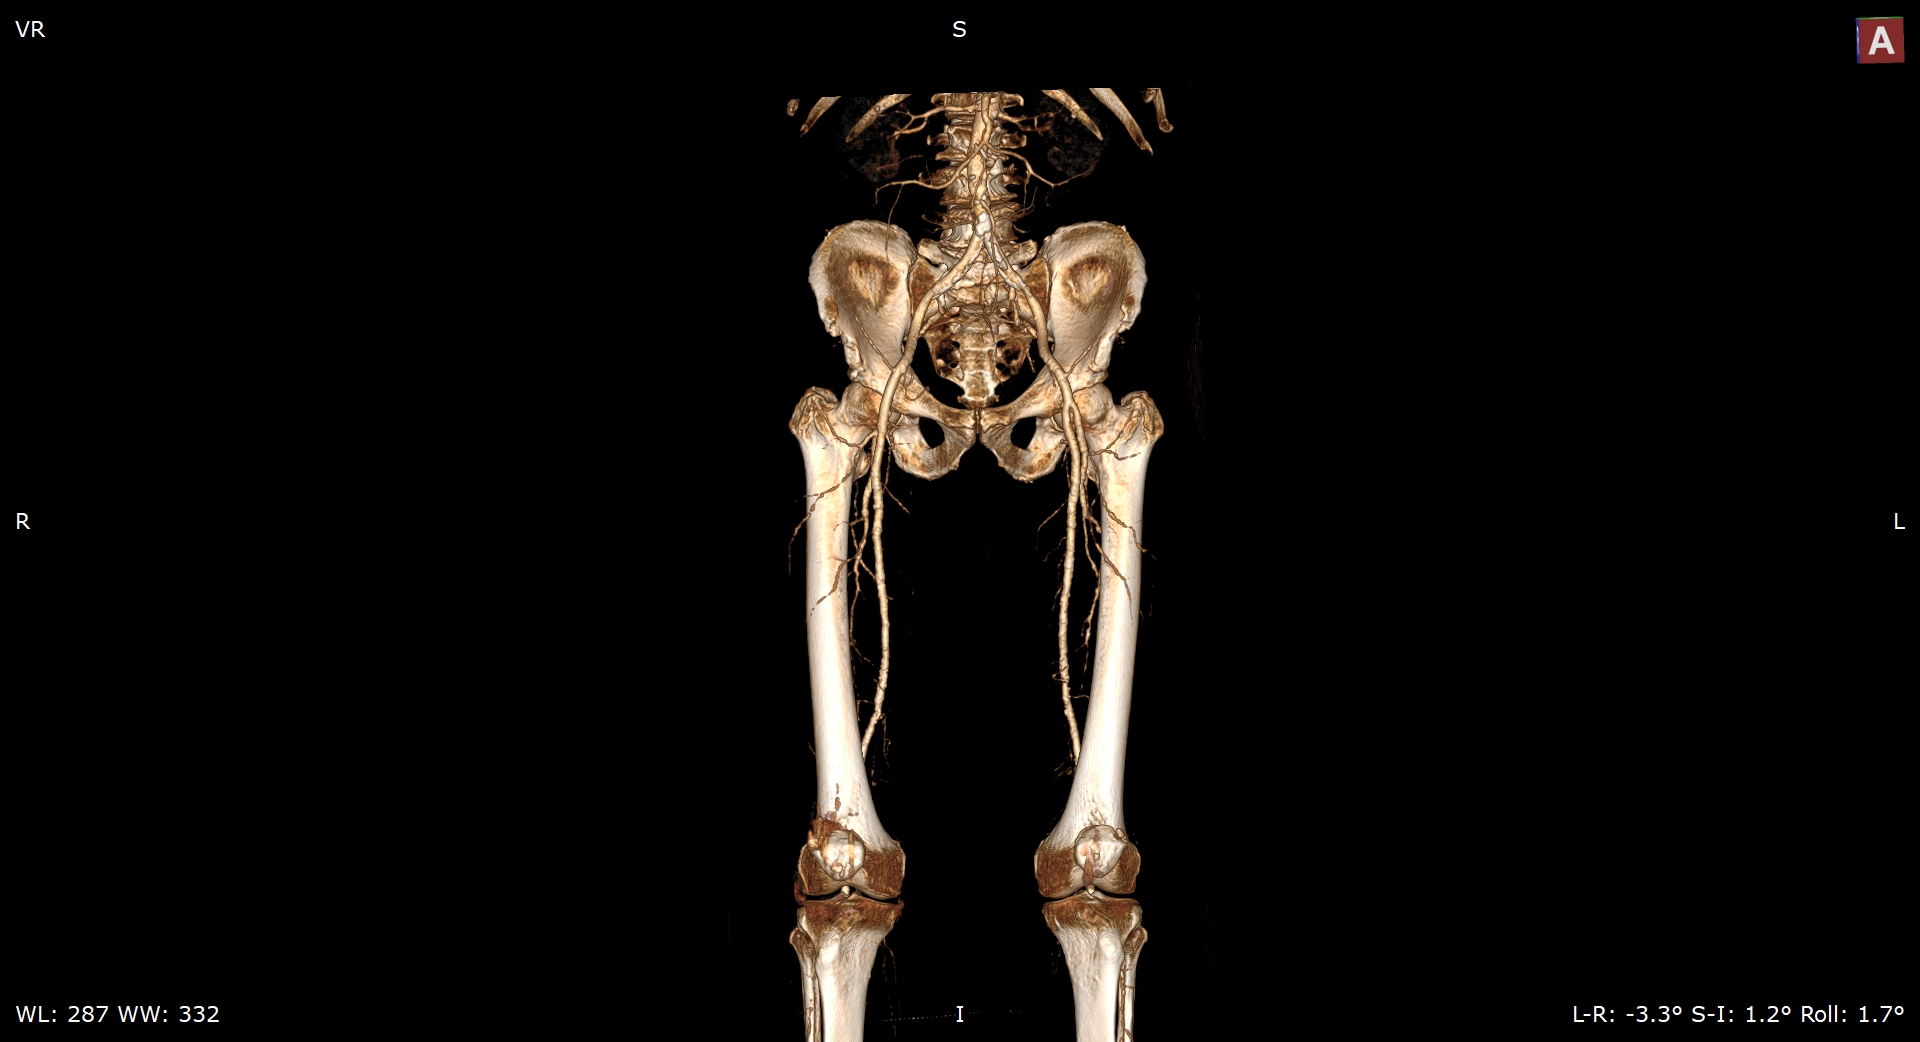

Мультиспиральная компьютерная томография является современным методом обследования сосудистой системы нижних конечностей. Такое исследование по-другому называется КТ-ангиография. Методика позволяет с помощью рентгеновского излучения получить посрезовые снимки и после цифровой обработки создать объемные модели кровеносной системы обеих ног.

В наших медицинских центрах КТ-ангиография нижних конечностей выполняется на современных мультиспиральных компьютерных томографах экспертного уровня TOSHIBA AQUILION. Аппараты послойно сканируют область исследования, одномоментно выполняя множество тончайших срезов. В результате получаются снимки высокого качества и трехмерные модели с изображением даже мелкой сосудистой сети нижних конечностей. При этом методика скоростного мультисрезового сканирования обеспечивает минимальную дозу рентгеновского облучения для пациента.

• КТ сосудов от бифуркации аорты до коленного сустава (оценивается нижняя часть брюшной аорты, разветвление аорты, подвздошные артерии, бедренные и подколенные артерии)

• КТ сосудов от бифуркации аорты до стопы (данный протокол обследования включает в себя полное обследование сосудов нижних конечностей, включая стопы)